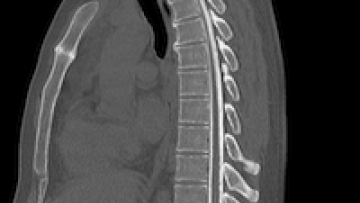

КТ позвоночника (полное название компьютерная томография позвоночника) - это неинвазивный способ обследовать костные структуры позвоночного столба. Преимуществом данного вида сканирования является его неинвазивность, высокая информативность и быстрота. В ходе обследования у врачей появляется возможность оценить анатомию позвонков, спинного мозга, суставов, нервных окончаний и сосудистого русла. Чаще всего в медицинской практике данное обследование используется неврологами, хирургами, травматологами...

Многие люди испытывают боли в спине. Распознать патологию, установить точную причину дискомфорта позволяет КТ. Это современная диагностическая методика, позволяющая получать снимки позвоночника в трехмерной проекции. С ее помощью можно обследовать весь позвоночник или конкретные отделы. Классическая КТ Наиболее востребована классическая КТ. В ходе проведения процедуры позвоночник обследуют при помощи рентгеновских лучей, которые направляют под разными углами. Информация передается в компьютерную программу, где происходит ее обработка...